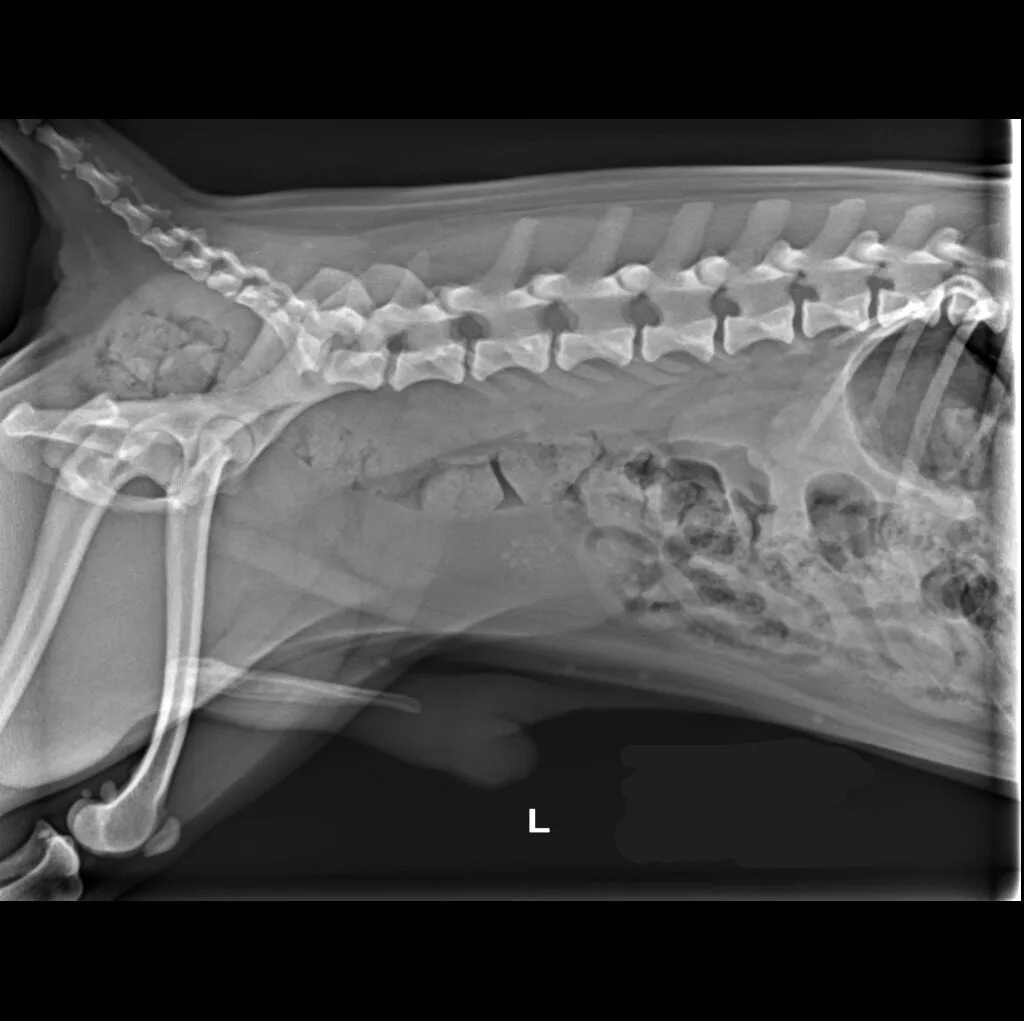

At Grand Ave. Pet Hospital, we utilize digital radiography to diagnose and monitor a wide range of medical conditions in pets. Digital X-rays provide clearer images, faster results, and safer radiation levels, ensuring the best possible care for your furry companion.

Digital radiography offers superior imaging quality and precision compared to traditional X-ray techniques. It allows us to detect hidden health issues early, leading to faster and more effective treatments.

🔹 Abdominal & Gastrointestinal Issues – Detecting obstructions, tumors, or organ abnormalities